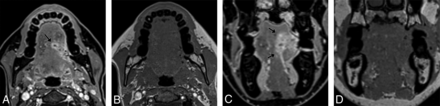

We began by optimizing T1-weighted gradient-recalled echo images, called the volumetric interpolated breath-hold examination (VIBE; Siemens) before T1-weighted TSE sequences were available across our scanners. The soft-tissue contrast on the VIBE images was subjectively considered poor by our neuroradiology faculty relative to the 2D and 3D TSE images, providing less contrast between fat and muscle, while blood vessels also had roughly similar intermediate signal intensity. We, therefore, turned to 3D T1-weighted TSE sequences as they became available across our fleet of scanners. We used the Sampling Perfection with Application-optimized Contrasts by using different flip angle Evolution (SPACE sequence; Siemens) and the Cube sequence (GE Healthcare). Our optimization work has been performed with the SPACE sequence on 3T systems, then applied to the Cube sequence, and then adapted for 1.5T systems. Direct comparisons of T1-weighted VIBE and SPACE images are provided for a 44-year-old woman with neck pain in Fig 1.

Sample 3D T1 VIBE (A), 3D T1 SPACE (B), and postcontrast 3D T1 VIBE Dixon fat-suppression (C) images acquired in the same session on a 3T Magnetom Vida system (Siemens) at the level of the oral cavity, retromolar trigone, and parotid glands in a 44-year-old woman with neck pain show excellent discrimination of soft-tissue structure boundaries with subjectively better soft-tissue contrasts on the SPACE than on VIBE and robust fat suppression on the VIBE Dixon.

For postcontrast imaging, the opportunity to acquire both T1-weighted in-phase images and fat-suppressed images in the same acquisition is highly appealing. The fat-suppression technique described by Dixon,9 in 1984, includes a single-sequence acquisition of both in-phase and opposed-phase data, allowing mathematic processing into 4 contrasts: T1-weighted in-phase, T1-weighted opposed-phase, T1-weighted water, and T1-weighted fat. The implementation of Dixon with a 3D spoiled gradient-echo sequence on Siemens systems is called VIBE Dixon, and on GE Healthcare systems, it is called liver acquisition with volume acceleration flex (LAVA Flex). Anecdotally, we have found the Dixon technique to be more robust than the spectral fat-suppression techniques we use in 2D imaging. Direct comparison of the T1-weighted VIBE Dixon fat-suppressed images is provided in Fig 1 in conjunction with the T1-weighted precontrast images from the same patient.